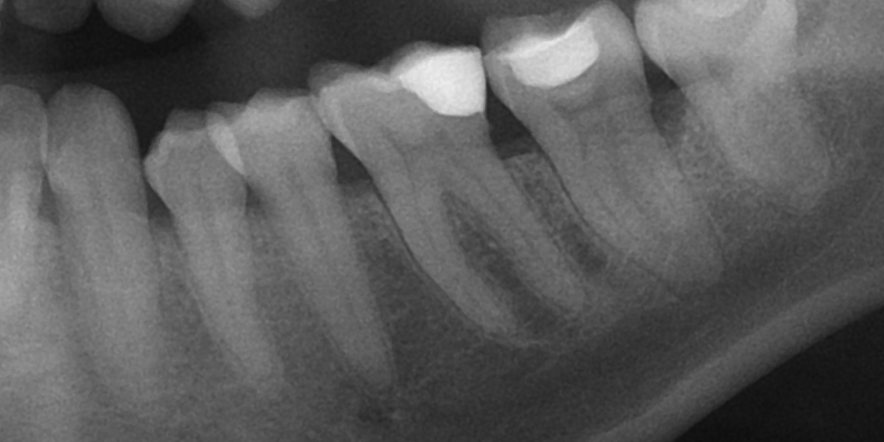

Dantų kanalų gydymas